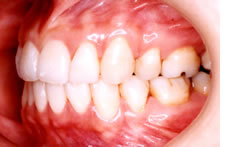

■治療前

相談に見えられた患者さんは、一見矯正治療が必要ないと思えるほど美しい20代の女性です。ですが、少し前歯が前方に出ており、口元に突出感があることを気にされていました。

■治療後

治療後のお口の中です。あたりまえのことですが上下の歯がきちんと咬んでいます。歯は、上下の歯が互い違いにきちんと咬むようにできています。